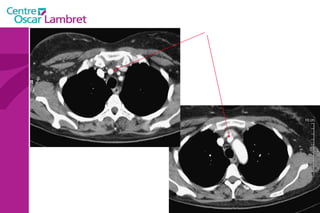

Les Troncs Supra Aortiques s’organisent autour de la trachée à leur origine. L’appareil circulatoire

Le  Tronc artériel Brachio-céphalique  : Naît de la face supérieure du 2e segment horizontal de la crosse aortique à hauteur de T 4. Volumineux, (diamètre 12 mm - longueur 3 cm) il se dirige en haut et à droite croisant la partie droite de la trachée. Derrière l’articulation sterno-claviculaire droite il bifurque en artères sous-clavière droite et carotide primitive droite.  L’appareil circulatoire

Les  artères Carotides Communes  : La droite vient du TABC. La gauche vient de la crosse de l’aorte. Elles n’ont aucune branche collatérale. L’appareil circulatoire

L’artère carotide primitive gauche  : naît directement de la crosse aortique et comporte un premier segment intra thoracique en arrière du manubrium sternal. Son segment cervical est identique à celui de la carotide primitive droite.  L’appareil circulatoire

Artères sous-clavières  : l’une à droite et l’autre à gauche. La droite naît du tronc brachio-céphalique moins longue que la gauche, elle se dirige obliquement en haut et en dehors.  La sous-clavière gauche, au contraire, naît directement de l’aorte, remonte verticalement en haut. Arrivées au niveau de la première côte, ces deux artères présentent la même disposition, deviennent horizontales, passent entre les deux muscles scalènes et prennent le nom d'axillaires.